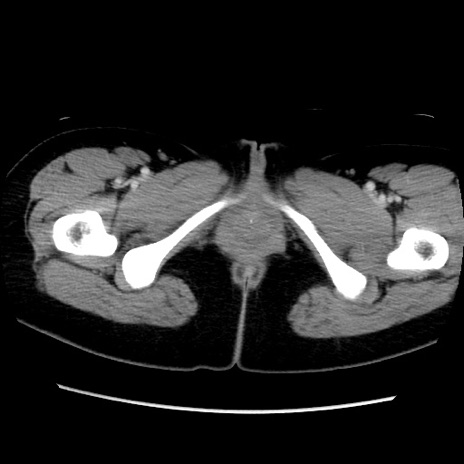

MRI(4日後)

【症例】40歳代女性

【主訴】上下腹部痛

【現病歴】2日目から下腹部痛あり。夜間は痛みで眠れなかった。昨日より上腹部痛と下痢が出現。臥位で痛みは軽快したため、休んでいた。本日になって臥位でも立位でも痛みが強くなってきたため救急要請。

【既往歴】子宮内膜症

【身体所見】部:平坦・軟、左上下腹部に圧痛あり、反跳痛あり。

【データ】WBC 21800、CRP 26.78